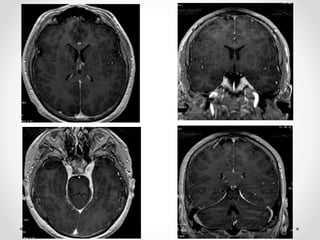

Xuất huyết Duret

- Là một hoặc nhiều ổ xuất huyết nhỏ ở cầu và hành não, sau

thoát vị qua lều hướng xuống, đặc biệt là thoát vị trung tâm.

Thường thấy ở BN có thoát vị trung tâm mức độ nặng từ 12-

24h trước khi chết

 Hình ảnh điển hình: một ổ xuất huyết tròn, nhỏ nằm ở đường

giữa hành não hoặc cầu não vị trí nối với cuống não.

 Chẩn đoán phân biệt:

- Xuất huyết do tăng huyết áp nguyên phát: thường lớn hơn,

nằm ở phần giữa cầu não, không có thoát vị não

- Dập não/ tổn thương sợi trục lan toả: ở mặt lưng của thân não(

quanh cống não và mảnh sinh tư), thường đa ổ và kích thước

nhỏ hơn

Xuất huyết Duret -Là một hoặc nhiều ổ xuất huyết nhỏ ở cầu và hành não, sau thoát vị qua lều hướng xuống, đặc biệt là thoát vị trung tâm. Thường thấy ở BN có thoát vị trung tâm mức độ nặng từ 12- 24h trước khi chết  Hình ảnh điển hình: một ổ xuất huyết tròn, nhỏ nằm ở đường giữa hành não hoặc cầu não vị trí nối với cuống não.  Chẩn đoán phân biệt: - Xuất huyết do tăng huyết áp nguyên phát: thường lớn hơn, nằm ở phần giữa cầu não, không có thoát vị não - Dập não/ tổn thương sợi trục lan toả: ở mặt lưng của thân não( quanh cống não và mảnh sinh tư), thường đa ổ và kích thước nhỏ hơn